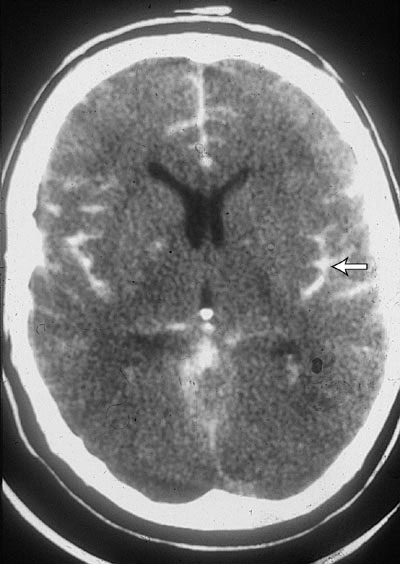

Subarachnoid Hemorrhage

This is Subarachnoid Hemorrhage (SAH). When you have a SAH bleed, the bleeding occurs closer to the delicate brain tissue, in the innermost layers covering the brain. These layers are weak, so the bleeding takes an irregular shape around the brain. Because these layers are fragile, and the bleeding occurs deeper in the skull, an operation to remove this blood is not likely to help.